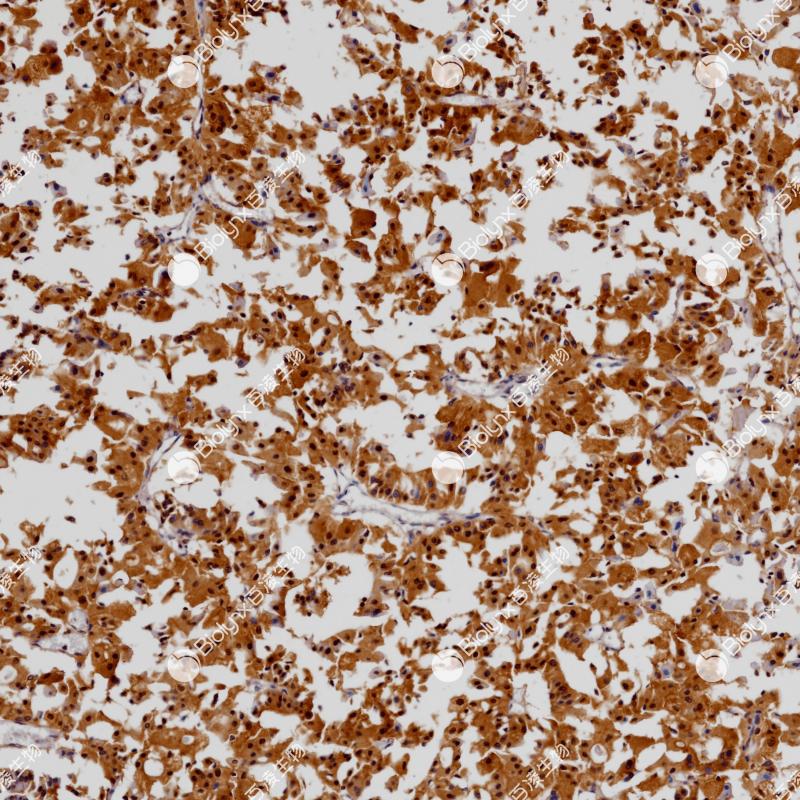

SATB2 重组兔单克隆抗体

SATB2是一种核基质附着区结合转录因子,在颅面、神经和成骨细胞分化中起重要作用。SATB2不仅表达于下消化道(阑尾、结肠和直肠)上皮,在发育中的皮质和脊髓神经元、成骨细胞、淋巴细胞、肾曲小管上皮细胞和脑神经元中也有表达。SATB2不仅是成骨细胞分化的标志物,也是结直肠癌的特殊标志物。SATB2在神经系统发育、骨骼发育和肿瘤细胞侵袭中发挥重要作用。

阳性对照

结肠癌

亚细胞定位

细胞核